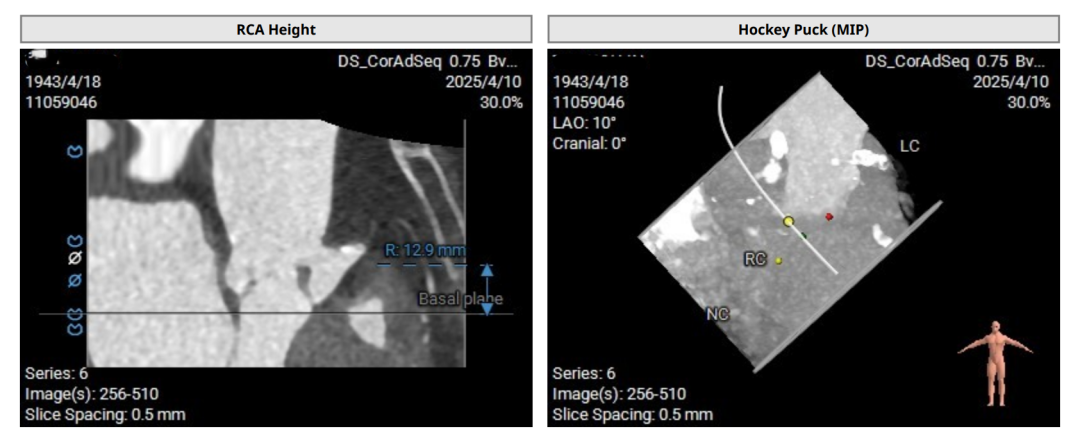

术前评估

术前CT(上下滑动查看更多图片)